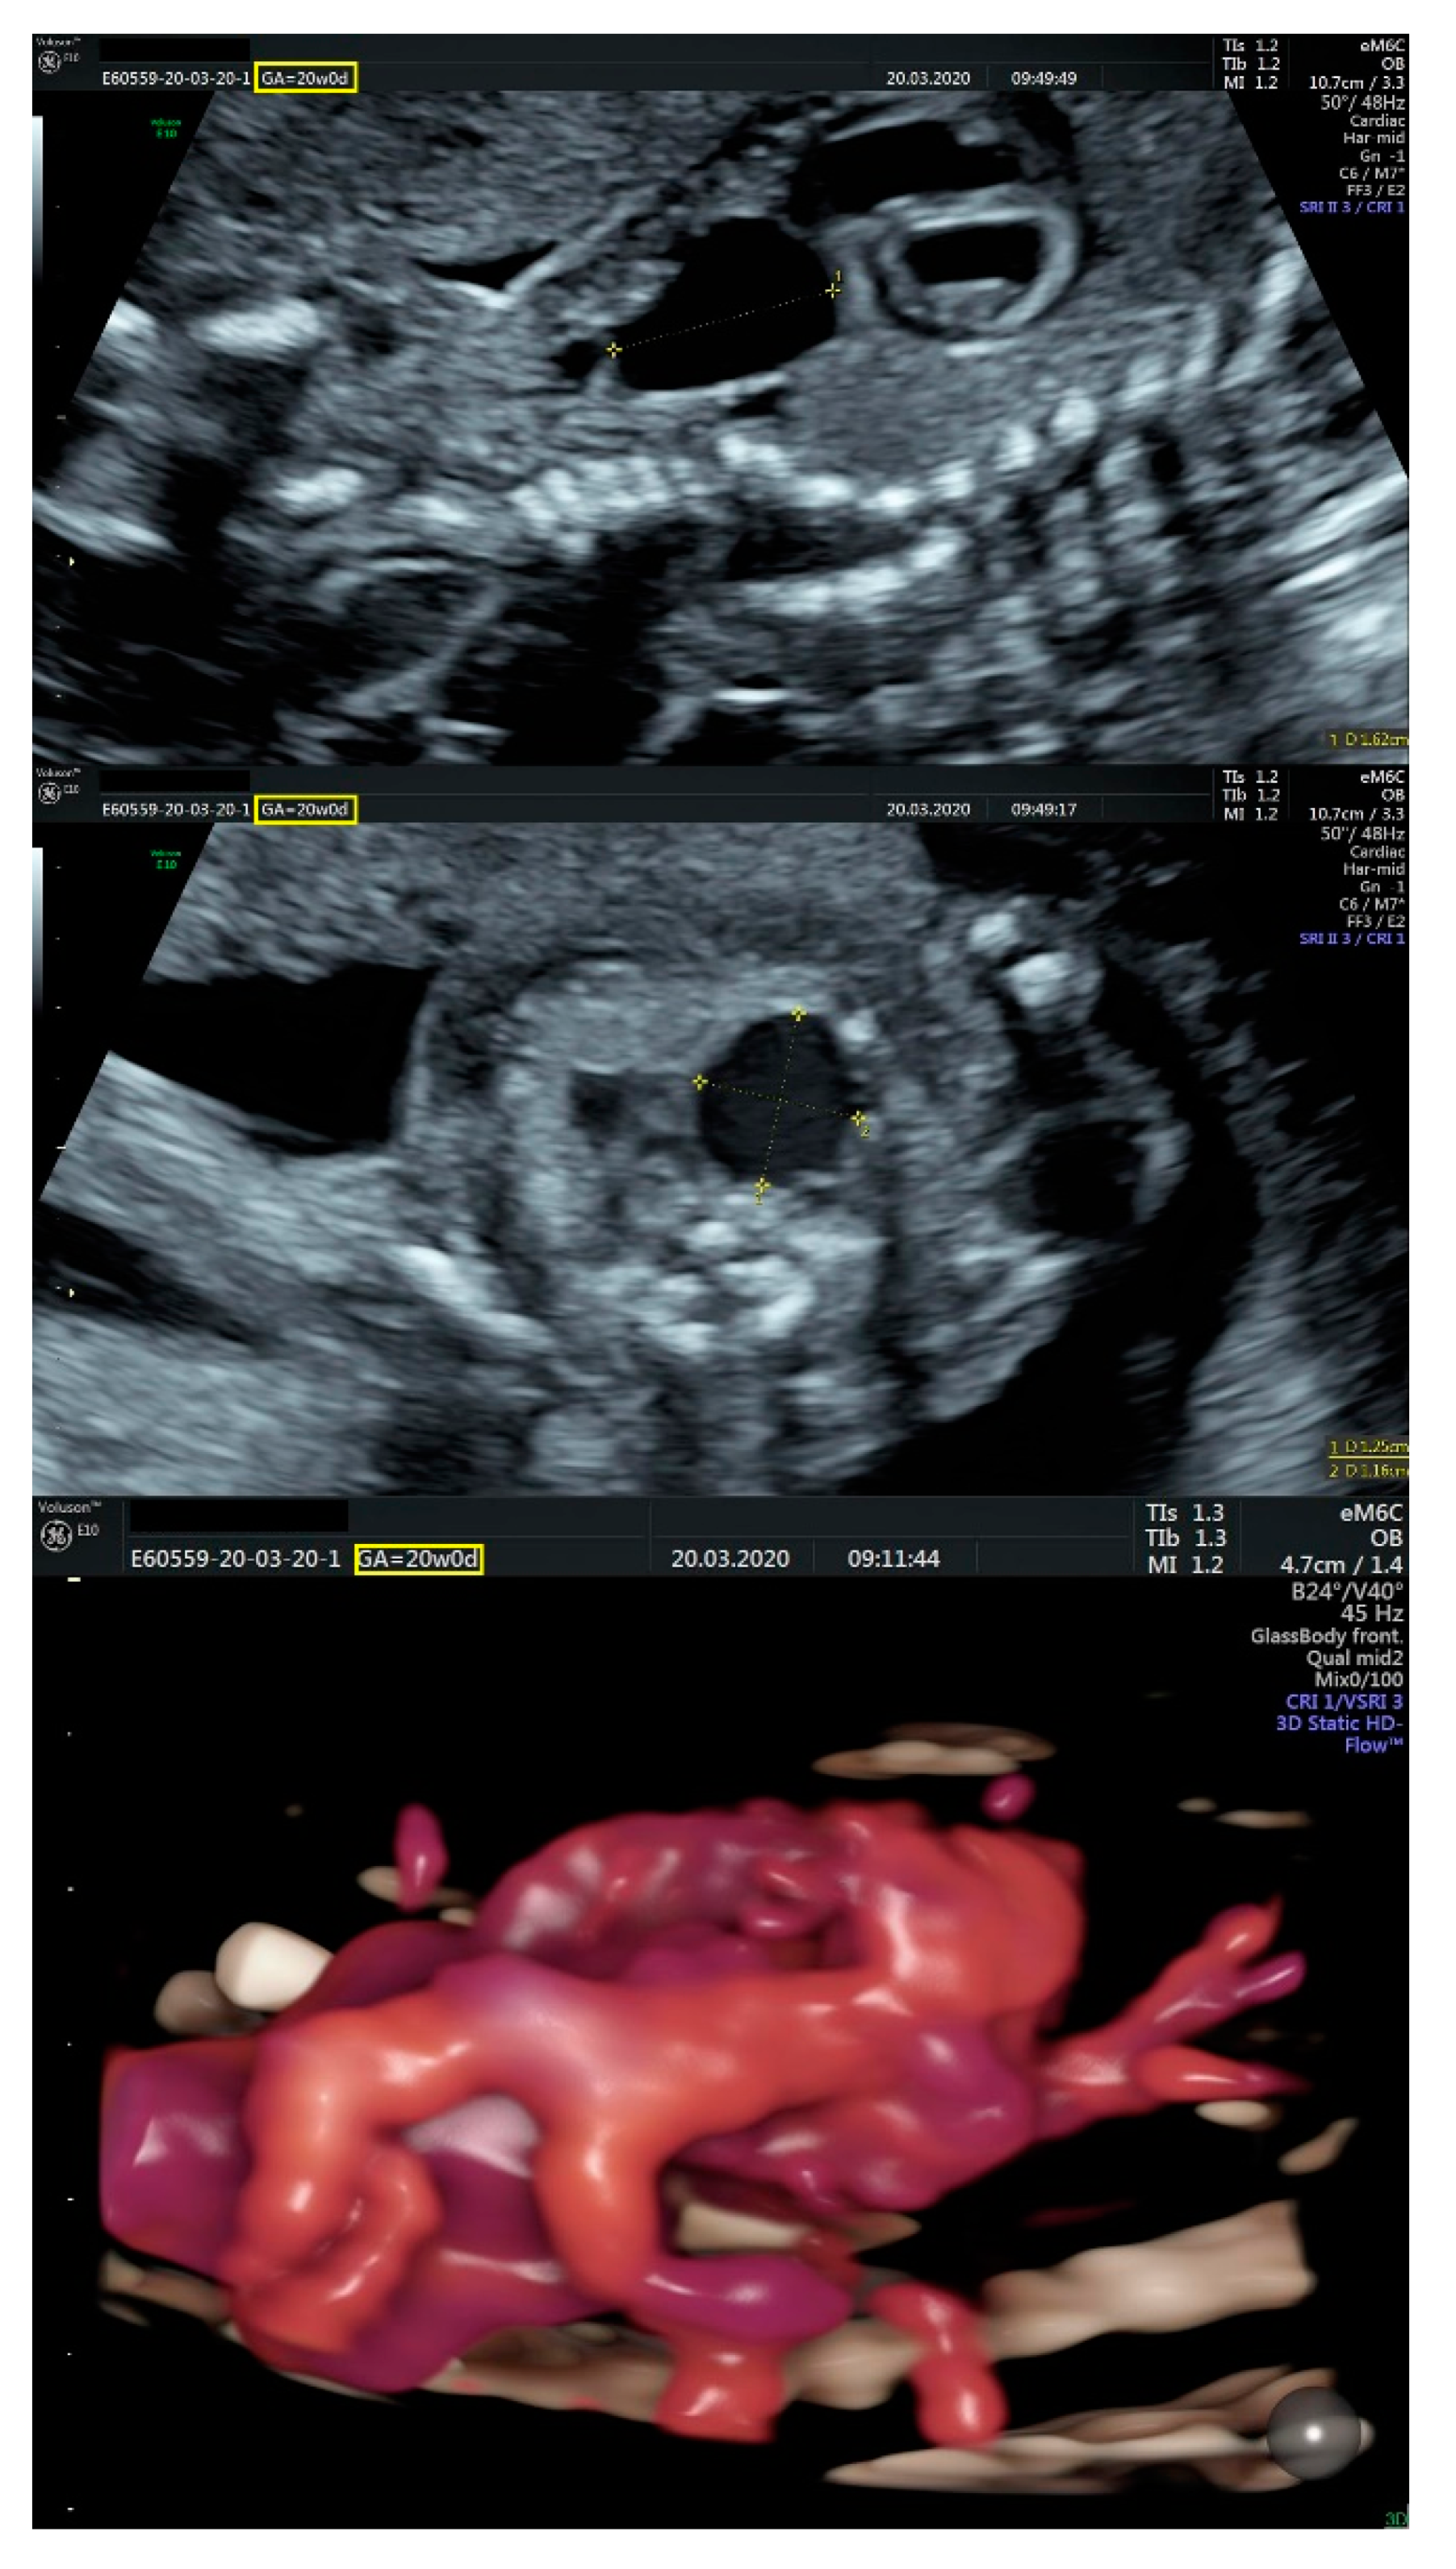

2.1. Ultrasound Findings

- an isolated aortic arch anomaly (supposedly aneurysmal dilation from which the left common carotid artery emerges) and coarctation of the aorta with the anterograde flow;

- ventricular septal defect, coarctation of the aorta, and a vascular formation located superior from the aortic arch with the appearance of an arteriovenous fistula;

- aneurysmal dilation located above the pulmonary trunk bifurcation and a dilated left common carotid artery with a retrograde flow;

- minor ventricular septal defect with a normal ductus venosus triphasic flow.